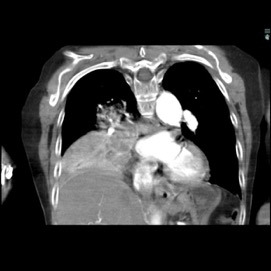

As part of the patient’s treatment, the thoracic surgery team performed a right middle and lower lobectomy. A 4-cm mass in the right bronchus intermedius without invasion into the lung parenchyma was revealed, and pathology confirmed the diagnosis of leiomyosarcoma. The sections of pulmonary tissue from the right middle and lower lobectomy showed a spindle cell tumor most consistent with leiomyosarcoma (Figure 3a-d). Most of the tumor was low grade, with some foci showing high-grade nuclear atypia and increased mitotic activity. Despite these rare mitotic figures, there was no evidence of necrosis. Following surgery, chemotherapy was planned for the patient. However, the patient’s postoperative course was complicated by persistent hypoxic respiratory failure, hypovolemic and hemorrhagic shock, and acute kidney injury. Her respiratory status continued to decline, and she went into cardiac arrest with pulseless electrical activity. She was resuscitated; however, her shock and respiratory failure worsened despite aggressive therapy. Her family chose to transition her to comfort care, and the patient died.

The immunohistochemistry staining also lent additional support to the diagnosis of leiomyosarcoma. As would be expected for such a diagnosis, both vimentin and desmin were immunoreactive. The tissue also stained positive for muscle markers including smooth-muscle actin, muscle-specific actin, and desmin, thus supporting the histological diagnosis of low-grade (highly differentiated) leiomyosarcoma. The tissue stained negative for S100, therefore pointing away from melanoma as a potential diagnosis. The immunohistochemistry profile also included pankeratin staining to distinguish a potential carcinosarcoma with sarcomatoid differentiation, and this test result returned negative.

The patient’s malignancy followed the typical behavior of endobronchial leiomyosarcoma. These tumors are expected to expand locally, although there was no evidence that her tumors had yet reached this stage of invasion. After lobectomy, surgical pathology of the mass obstructing the bronchus intermedius demonstrated that the tumor had not invaded the visceral pleura, nor were there positive margins at the bronchial, vascular, or parenchymal margins. The tumor was 1 cm from the closest margin. Also in alignment with the diagnosis of a low-grade leiomyosarcoma, there was no evidence of malignant spread to any of the 4 lymph nodes histologically examined, and Ki-67 staining highlighted less than 5% of cell nuclei in the right lung mass and less than 1% of cell nuclei in the left lung mass. Her tumor staging was pT3 pN0.